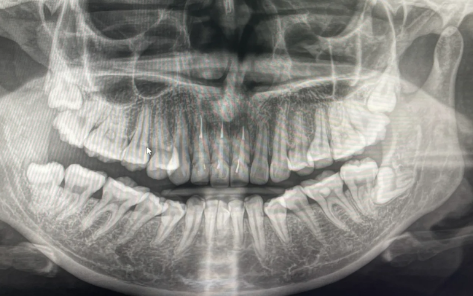

经过多年的临床经验观察有些人拔掉智齿确实会出现面部凹陷的情况,类似于牙套脸!网络上许多说拔完智齿带牙套许多形成牙套脸没恢复的其实就是因为拔智齿的原因,因为智齿拔掉以后有些人会出现末端牙槽骨凸吸收会形成不可逆的面容苍老。